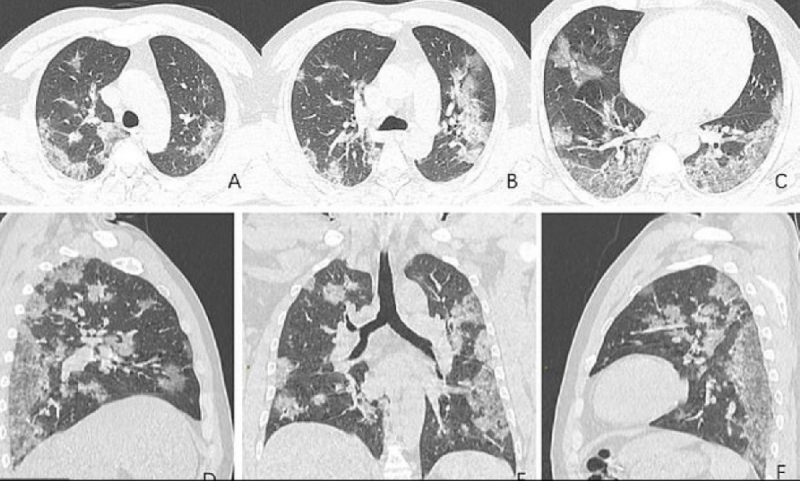

CORONA CİĞERLERE ETKİSİ ORTAYA ÇIKTI

Öte yandan merkezi ABD’de bulunan Kuzey Amerika Radyoloji Topluluğu tarafından paylaşılan röntgen görüntüleri corona virüsünün ciğerlere nasıl etki ettiğini gözler önüne serdi. Uluslararası basın kuruluşlarına yansıyan görüntülerde Whan’daki deniz ürünleri pazarında çalışan 44 yaşındaki bir corona virüsü hastasının ciğerlerindeki doluluk oranı görülüyor.